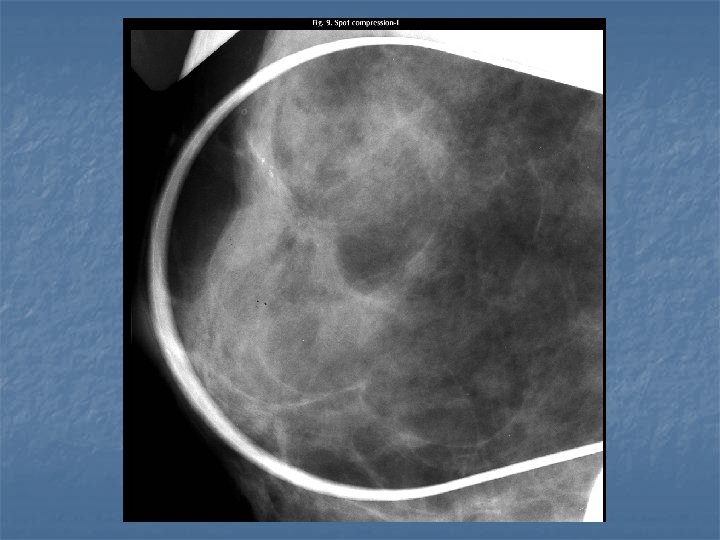

Radial scar n Case findings: n n n 7 mm density in retroareolar location in the left breast, with radiating linear strands surrounding it Best seen on the CC view Spiculated lesion, central nidus with internal radiolucencies ( white star) Predominantly radiolucent spiculations (rather than radiodense) Requires open surgical biopsy malignancy present in 25% of cases (some are invasive carcinomas, but others are radial scars that have small internal or adjacent areas of carcinoma) Open surgical biopsy: less subject to sampling error than are percutaneous biopsy procedures (aspiration or core biopsy)